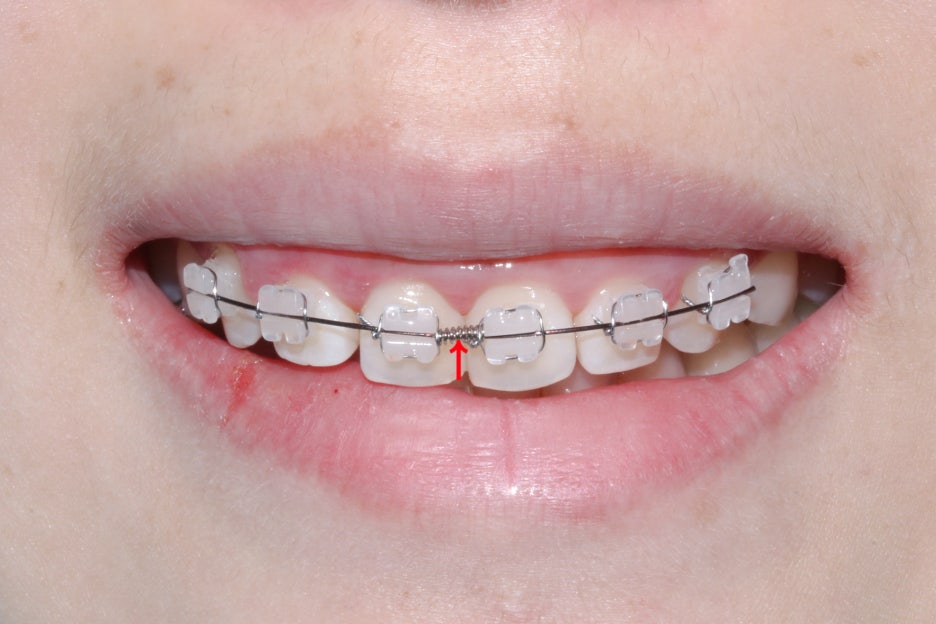

세라믹교정 전 전치부의 모습입니다.

살짝 미소를 지으면 드러나는 스마일라인에서

상악 중절치의 치축이 틀어진 모습을 확인할 수 있는데요,

정상적인 치아의 경우 중절치의 치축은

수직으로 배열되어 있어야 하지만 위의 Case에서는

중절치 2개가 나비치아 증상을 보이며 삐뚤어진 모습입니다.

세라믹교정 초기에는 위처럼 본격적인

치아교정을 위한 브라켓을 부착하게 되는데요,

위의 Case는 상악 전치부만 부분교정을 진행하기 때문에

6개의 치아에만 브라켓을 부착한 상태입니다.

세라믹 교정장치는 위처럼 치아색상과 유사한

세라믹 소재의 브라켓을 사용하기 때문에

심미성이 높은 편인데요, 다만 가로로 지나가는

교정철사와 ligature wire가 노출되기 때문에

2D교정이나 투명교정과 같은 완벽한 심미성은

기대하기 어렵습니다.

유의미한 교정효과가 보장되기 때문에

여전히 많은 사랑을 받는 교정 장치입니다.